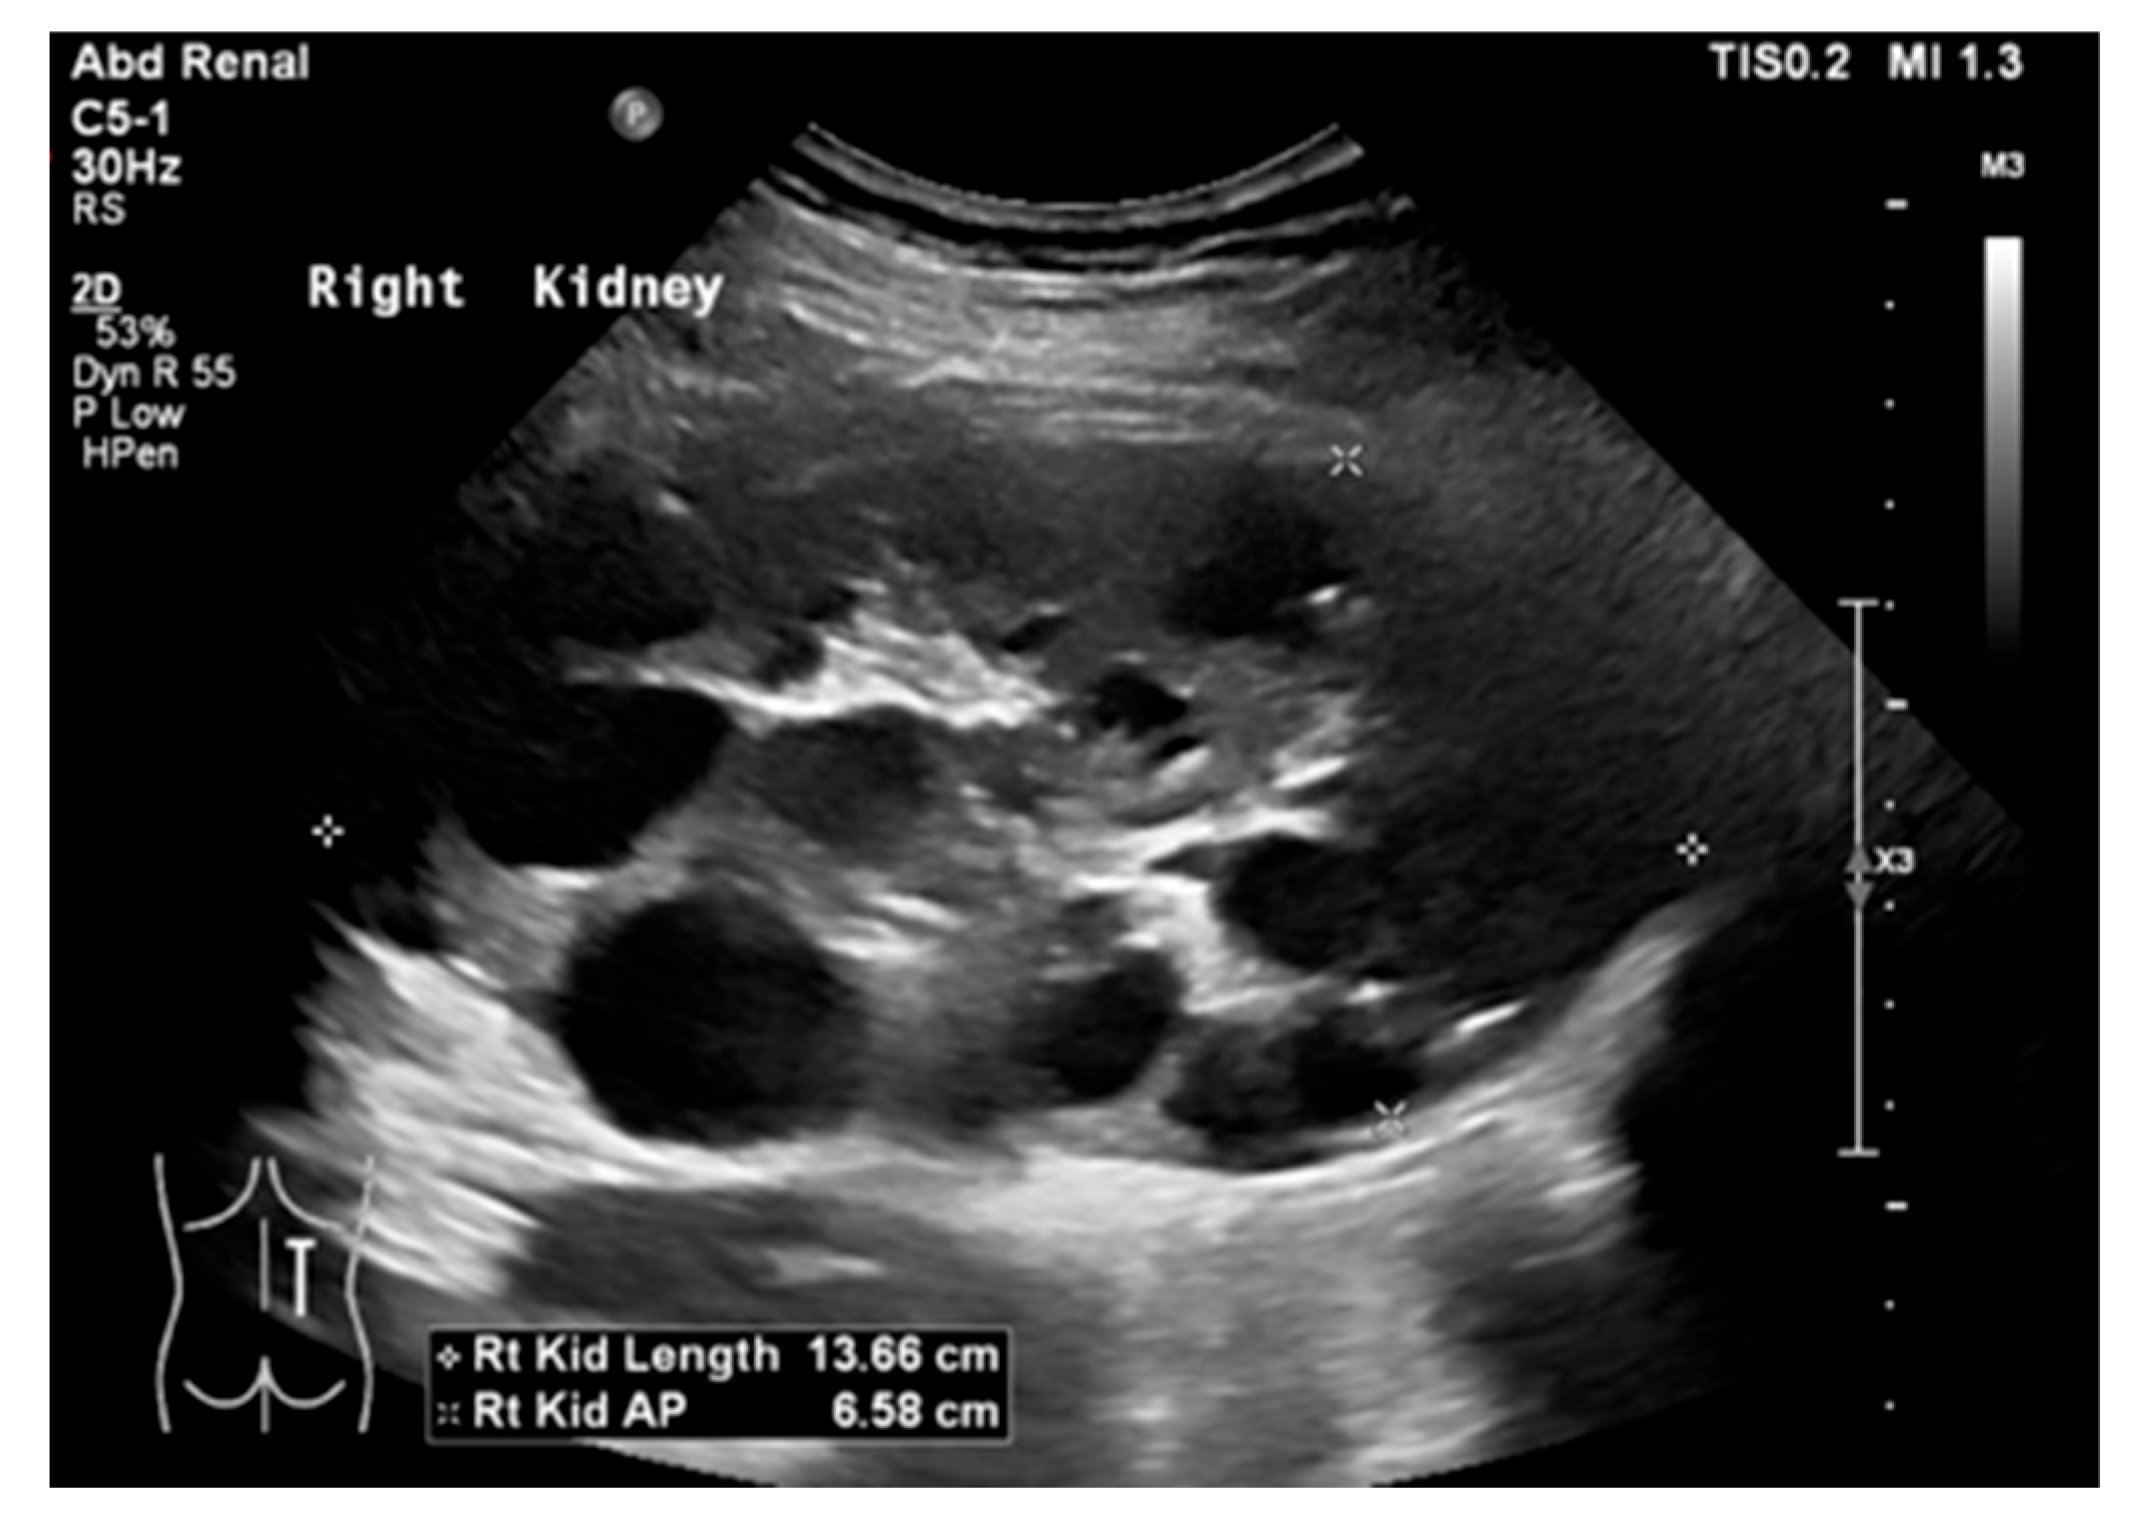

17. Cystic Kidney Disease

18. Tuberous Sclerosis